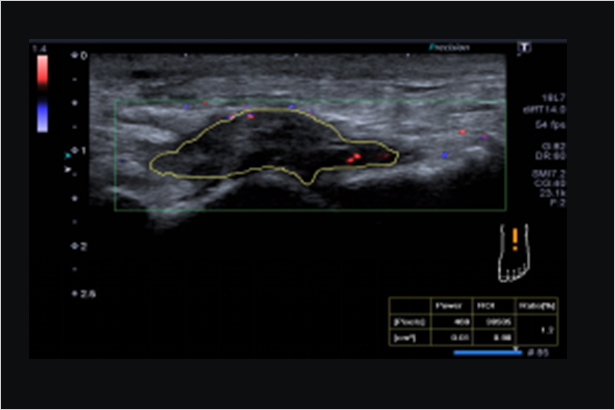

SMI帶來精細和清晰的彩色多普勒血流成像。SMI擴展了可見血流的范圍。低速微血流,SMI可以呈現

FLEX-M組件通過對視野內彩色像素數量的計算,定量評估血流豐富程度

ADF運用寬頻帶窄脈沖技術讓多普勒成像模式具有敏感度和空間分辨率